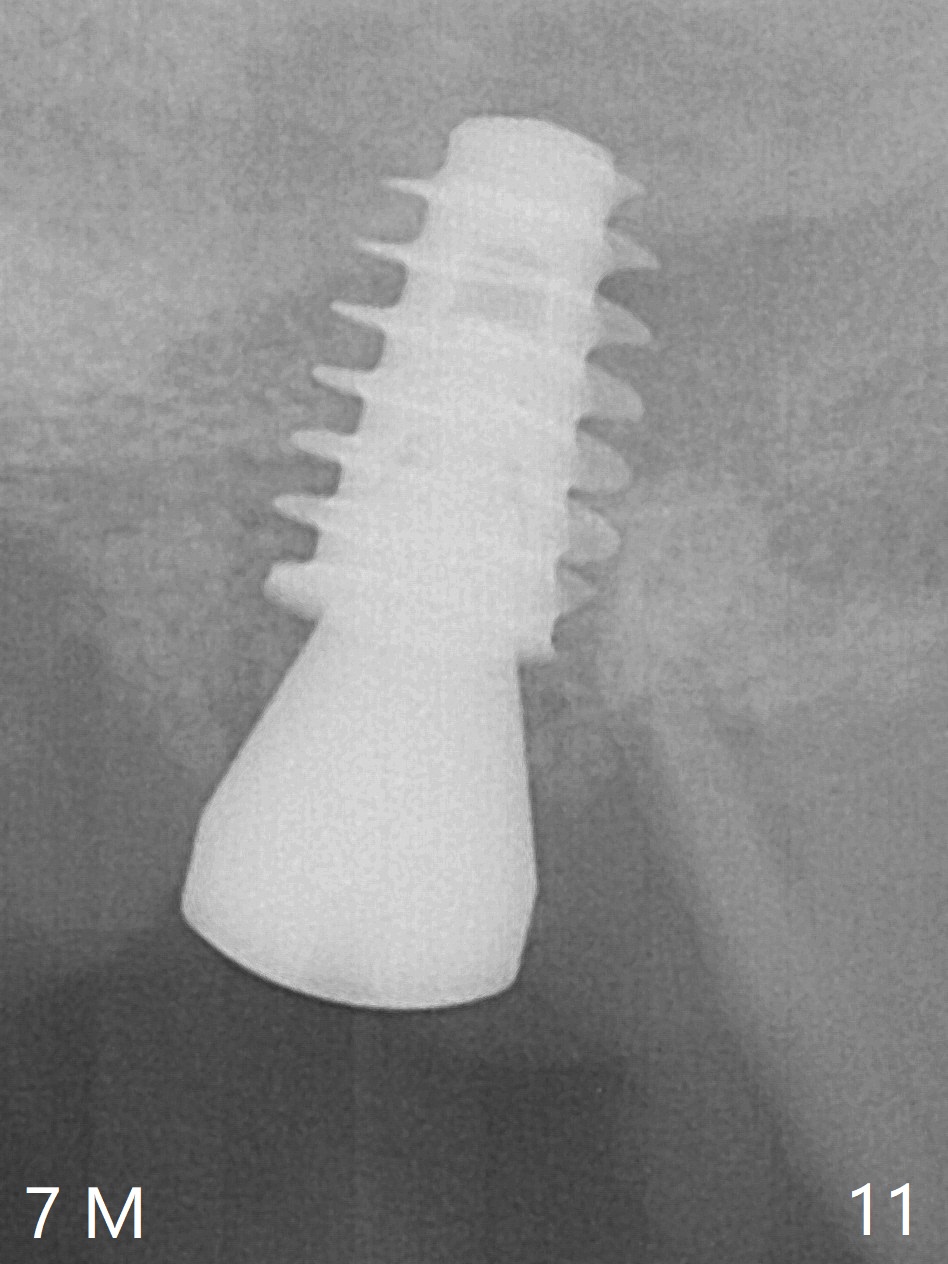

One month later, bone graft is placed mesiopalatal to the implant at #15 (Fig.7 *,8) while a 3.8x13 mm implant is placed at #13 following bone expansion (using Magic Split and Magic Expander 3.0 mm (abutment 5.5x4(5) mm). Another month later, the tooth #16 is extracted to create space for #15 restoration. Two weeks later the abutment at #15 is found to be unstable (2.5 months postop). Local oral hygiene is poor. The abutment is removed and a 6x4 mm healing abutment is placed with mild tenderness. It appears that the limited bone height is associated with low stability with CMC. Three months later (5.5 months postop), the implant seems to be stable (Fig.9,10). The implant remains stable clinically 7 months postop (Fig.11). The bone graft appears to mature and covers the abutment with provisional 24 months postop, the bony changes is related to the thick gingiva (Fig.12 ^).